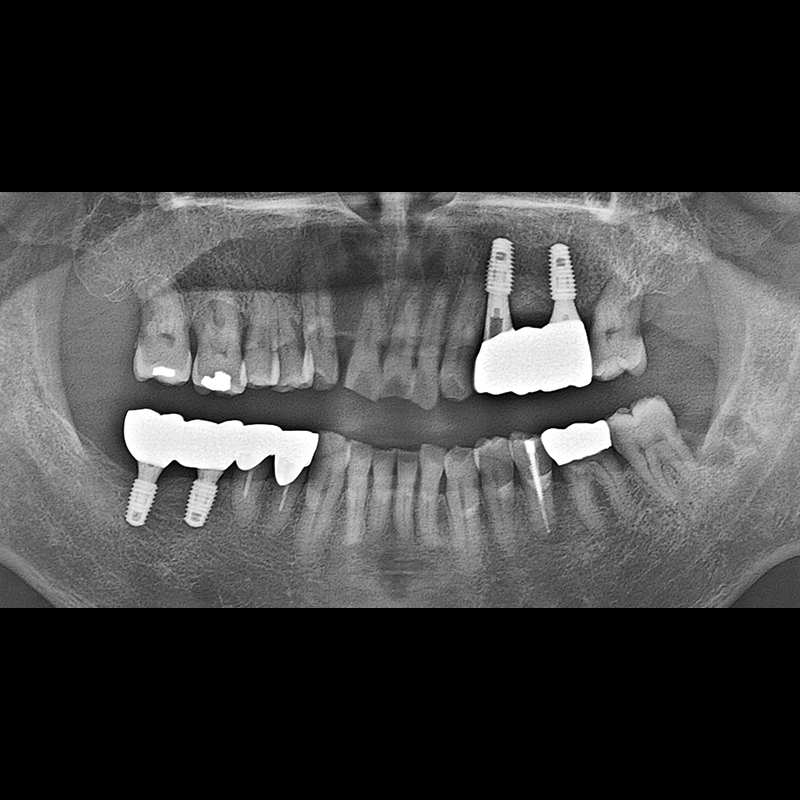

IMPLANT

BEFORE AFTER